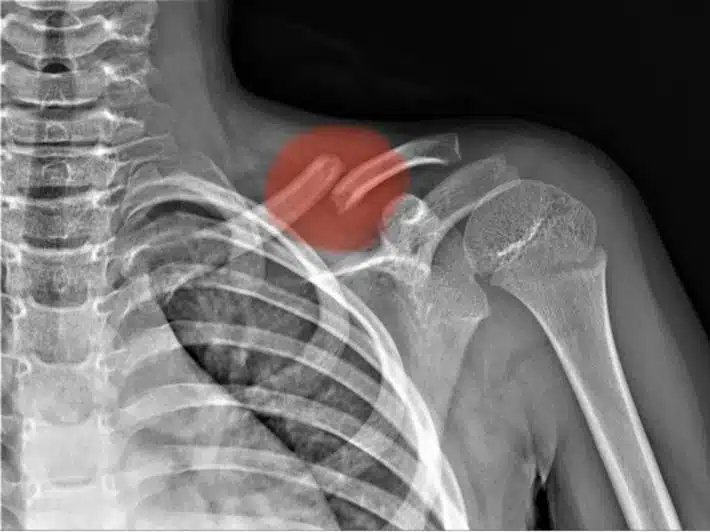

أنواع كسر الكتف وطرق العلاج

كسر الكتف هو عبارة عن تعرض عظام الجزء العلوي من الذراع للكسر ويكون ذلك قريباً بشكل كبير من مفصل الكتف، وتختلف شدة الإصابة التي تتواجد في منطقة الكتف وفقاً لمدى شدة الاصطدام الذي قد تعرض له الفرد سواء أكان ذلك متسبباً في حدوث للكتف بشكل تام أو حدوث كسر في لوح الكتف أو الترقوة أو العضد.

كسر الترقوة

عظمة الترقوة تكون طويلة ورقيقة ويبدأ امتدادها من قاعدة العنق وصولاً إلى الكتف، وهذا النوع من الكسور قد يصاب به الأفراد في أي مرحلة عمرية.

هذا النوع من الكسور يحدث بسبب السقوط أو التعرض لإصابة قوية في الكتف أثناء ممارسة بعض الرياضات مثل الهوكي أو قد ذلك بسبب التعرض لحادث.

كيف يتم تشخيص كسور الكتف؟

- الأشعة السينية.

- الأشعة المقطعية.

- عمل تصوير بالرنين المغناطيسي.

- الموجات الفوق صوتية على العضلات الهيكلية.